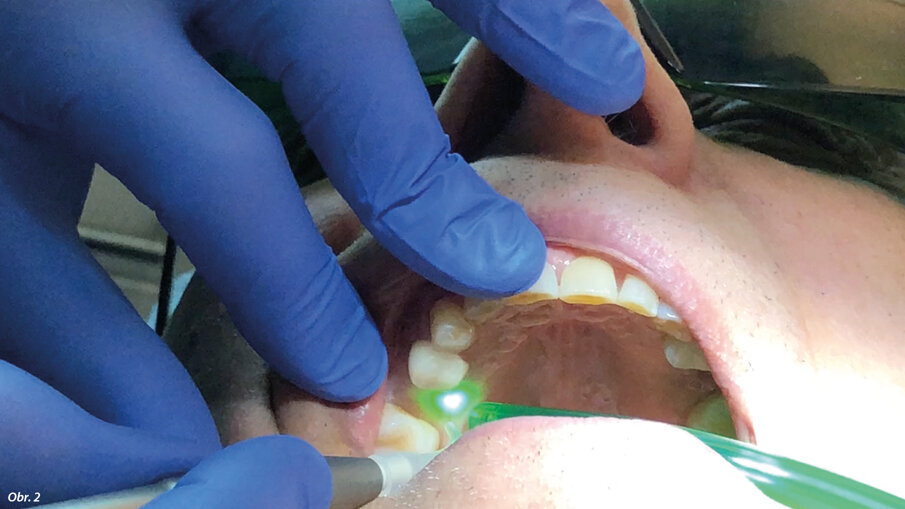

67letý pacient, nekuřák, bez jakýchkoli systémových onemocnění, byl vyšetřen pomocí CBCT (PaX-i3D Smart, Vatech) za účelem vyhodnocení operované oblasti, objemu kosti a hustoty kosti v bezzubé oblasti zubu 15 (obr. 1). Před chirurgickým zákrokem obdržel pacient veškeré informace týkající se ošetření a prostřednictvím individuálního informovaného souhlasu byl informován o možných alternativách ošetření. Osa zavedeného implantátu byla naplánována s ohledem na dosažení nejlepšího funkčního výsledku náhrady. Pro intraorální oporu Er:YAG násadce ve správné poloze odpovídající ose zavádění implantátu byl vytvořen individuální držák z dentální pryskyřice. Byla aplikována lokální anestezie ve formě artikainu (1 : 100 000). Pomocí Nd:YAG laseru (vlnová délka 1 064 nm; vlákno o průměru 200 μm; MSP: 3 W, 70 Hz; LightWalker AT, Fotona) byl na palatinální paramediální linii proveden mukoperiostální řez a současně s ním i dva meziální a distální uvolňující řezy nezasahující papilu (obr. 2). Přístupový lalok pak byl odklopen Prichardovým elevátorem (obr. 3).

„Incize“ laloku pomocí laserové hlavice LightWalker Nd:YAG (vlákno o průměru 200 μm, 3 W, 70 Hz, MSP).